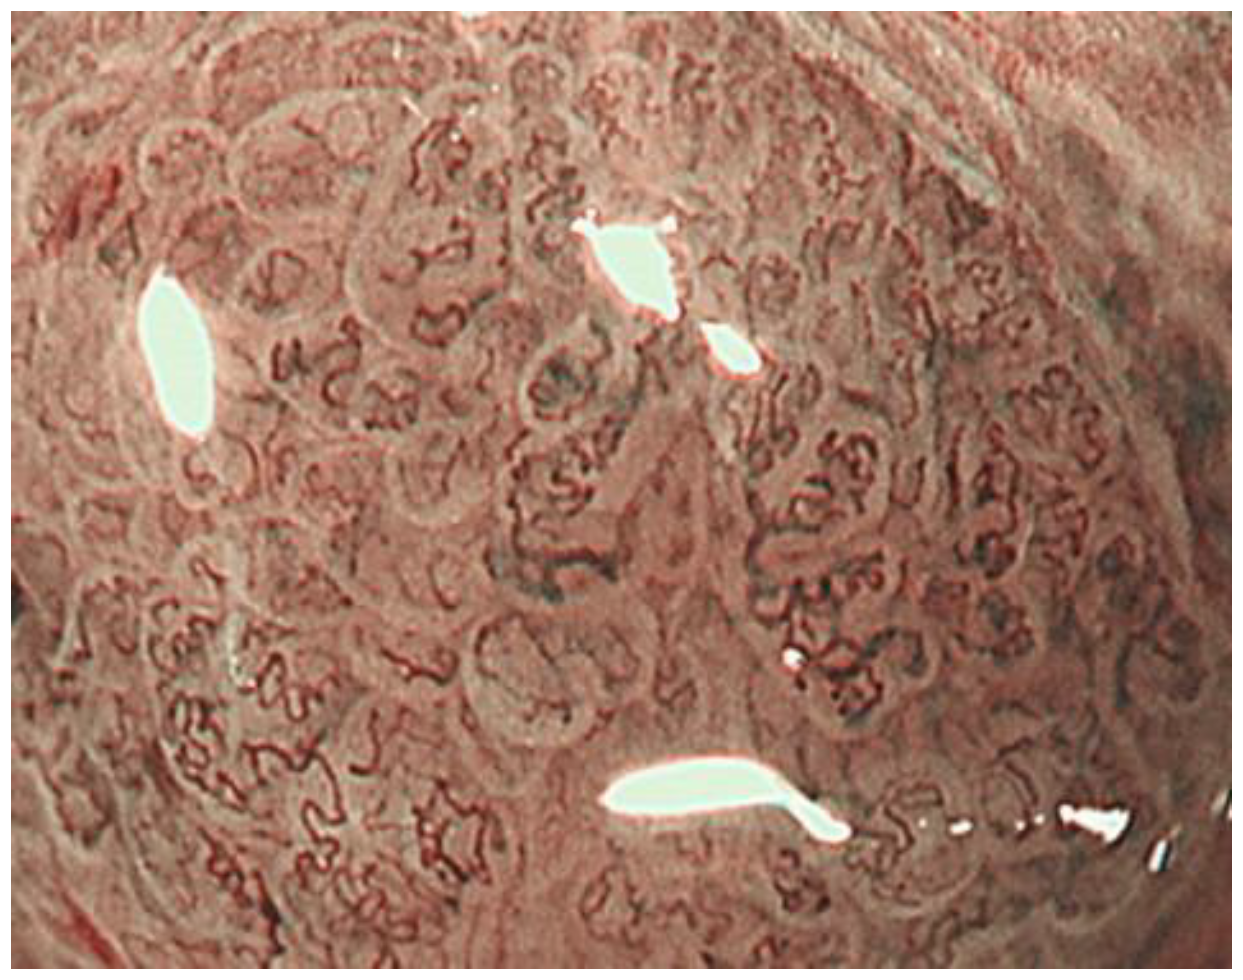

2.3. Inference of Histopathological Type of Gastric Cancer by ME-NBI

- Kanemitsu, T.; Yao, K.; Nagahama, T.; Fujiwara, S.; Takaki, Y.; Ono, Y.; Matsushima, Y.; Matsui, T.; Tanabe, H.; Ota, A.; et al. The vessels within epithelial circle (VEC) pattern as visualized by magnifying endoscopy with narrow-band imaging (ME-NBI) is a useful marker for the diagnosis of papillary adenocarcinoma: A case-controlled study. Gastric Cancer Off. J. Int. Gastric Cancer Assoc. Jpn. Gastr. Cancer Assoc. 2014, 17, 469–477. [Google Scholar] [CrossRef] [PubMed] [Green Version]